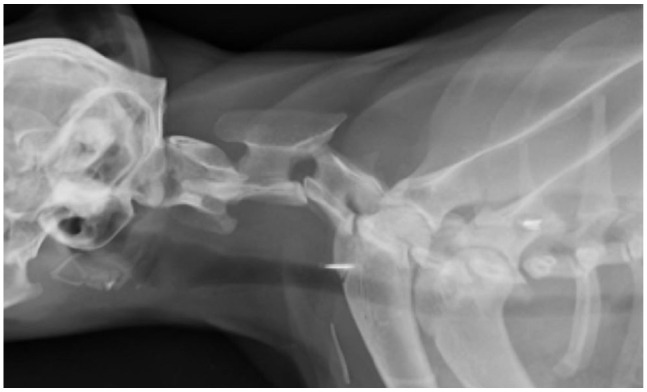

病例摘要:一只两岁大的绝育雌性短毛猫在一次交通事故后出现四肢瘫痪。脊柱放射线检查显示,C2-C3 颈椎脱位,CT 扫描证实了这一点。通过腹侧入路使用螺钉和聚甲基丙烯酸甲酯(PMMA)进行了手术稳定。术后 CT 扫描显示,植入物的位置正确,半脱位得到了很好的缓解。术后,猫咪的神经功能迅速恢复正常:外伤引起的颈椎半脱位在猫科动物中并不常见,但应在鉴别诊断中予以考虑。本报告描述了使用螺钉和 PMMA 对猫的 C2-C3 颈椎脱位进行手术治疗的情况。这是首例通过手术治疗猫颈椎轴下脱位的病例报告。

Case summary: A 2-year-old spayed female domestic shorthair cat presented with tetraparesis after being involved in a road traffic accident. Survey spine radiographs revealed a C2-C3 cervical subluxation, which was confirmed by a CT scan. Surgical stabilisation was performed using screws and polymethyl methacrylate (PMMA) via a ventral approach. A postoperative CT scan demonstrated correct implant positioning and good reduction of the subluxation. After surgery, the cat rapidly recovered to a neurologically normal status.